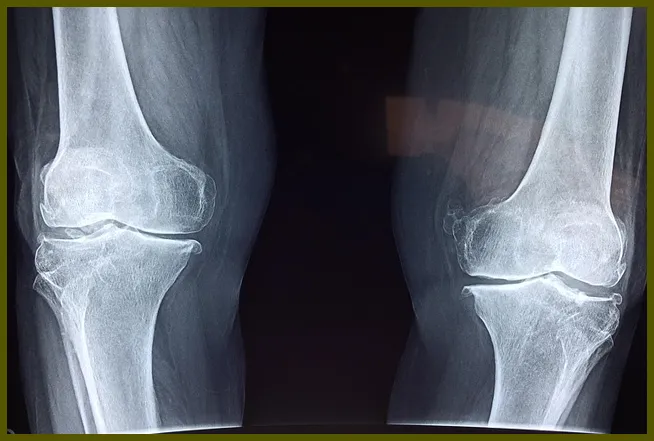

무릎 연골은 뼈와 뼈 사이에서 충격을 흡수하고 움직임을 원활하게 만드는 역할을 합니다. 이 연골이 손상되면 여러 가지 불편함을 초래하는데, 주로 무릎의 통증, 부기 및 운동 범위 제한 등이 발생합니다. 연골 손상은 일반적으로 외부 충격이나 과도한 운동에 의해 발생합니다. 예를 들어, 농구나 축구와 같은 스포츠에서 뛰거나 이동하는 과정에서 갑작스러운 움직임이 있으면 연골이 손상될 수 있습니다.

- 퇴행성 변화: 나이가 들면서 나타나는 관절의 자연적인 변화

무릎 연골 손상의 증상

무릎 연골 손상은 여러 가지 증상을 동반합니다. 초기 증상은 미미할 수 있지만, 시간이 지나면서 점점 심해질 수 있습니다. 다음은 가장 흔한 연골 손상 증상입니다:

- 무릎 통증: 가장 흔하게 느껴지는 증상으로, 무릎을 움직일 때나 체중을 실을 때 더욱 두드러집니다.

- 부기: 무릎 주위에 부풀어 오르거나 붓는 현상은 무릎 부상을 나타내는 신호일 수 있습니다.

- 움직임 제한: 무릎의 운동 범위가 줄어들어 일상생활이 불편해질 수 있습니다.

- 소리: 무릎을 움직일 때 '딱딱' 소리가 나거나 '파삭'거리는 소리가 날 수 있습니다.